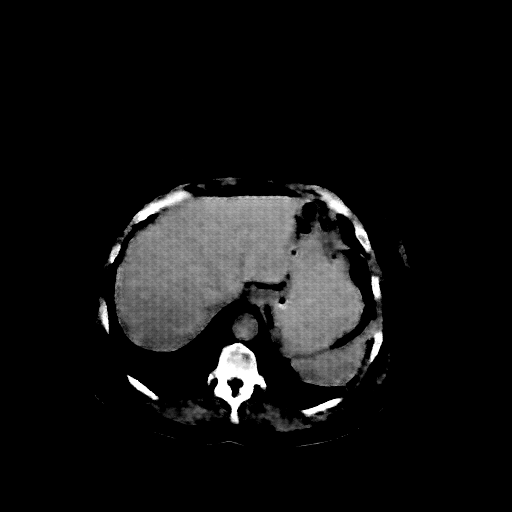

Original NATIVE CT scan (input)

Full window (WL 1023.5, WW 4095 β†’ Low βˆ’1024, High +3071)